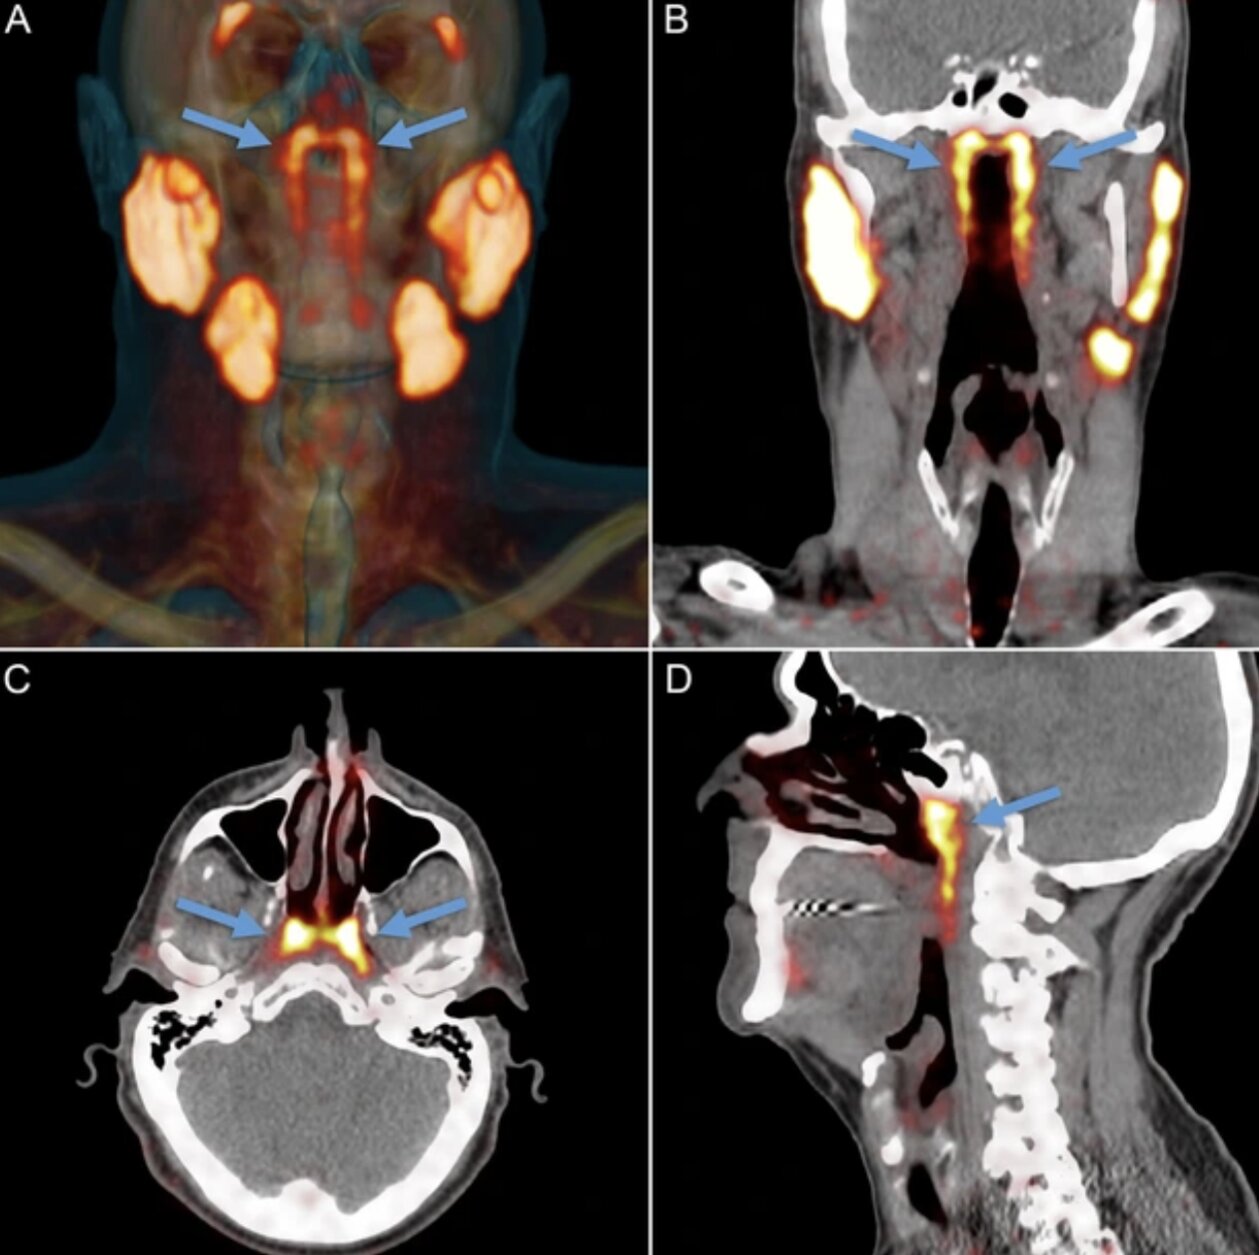

Theo NKI, câu chuyện bắt đầu không phải từ phòng mổ giải phẫu mà từ… máy PET/CT cho bệnh nhân ung thư tiền liệt tuyến. Khi các bác sĩ tiêm chất đánh dấu và soi hình ảnh, họ thấy hai vùng sáng bất thường ở vòm họng xuất hiện nhất quán trong hàng loạt bệnh nhân đã gợi ý có một cấu trúc tuyến lớn hơn những "tuyến nhỏ rải rác" mà sách y đã mô tả trước đó. Khám nghiệm thêm trên xác và phân tích mô cho thấy tồn tại mô tuyến với nhiều ống dẫn, đủ để các tác giả đặt vấn đề đây là một "vùng tuyến" có thể coi là cơ quan.

Theo PubMed, vào năm 2020, các nhà nghiên cứu Hà Lan công bố phát hiện một cặp tuyến nước bọt mới nằm ngay phía sau mũi, trong khu vực nối giữa khoang mũi và họng. Sau đó, nó đã được các chuyên gia đặt tên là tuyến nước bọt ống hầu (tubarial salivary glands). Phát hiện này lập tức làm dậy sóng truyền thông và cộng đồng khoa học vì nếu đúng, nó sẽ bổ sung vào "bản đồ" giải phẫu người vốn tự hào có 3 cặp tuyến nước bọt lớn đã được biết đến lâu nay.